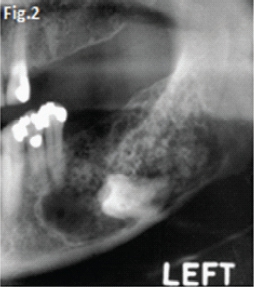

This 22 year old male patient (Figs.1 & 2) presented with a slow growing swelling in the left mandibular molar region. Figures 3, 4, 5 & 6 are images of three other patients with the same condition. Discuss the radiological features and what is your diagnosis?

Fig 1 & 2: the large lesion of left mandible shows a honeycomb-like distribution of calcifications. The borders are corticated. The tumour has displaced the mandibular molar tooth. A histological diagnosis of calcifying epithelial odontogenic tumour (Pindborg Tumour) was made. Fig.3 shows a Pindborg tumour distal to left second premolar associated with displacement of the first molar tooth. Fig.4 shows a similar tumour with mixed lucency-opacity between right premolar and molar teeth. Figs 5 & 6 show coronal and axial CT views of a large Pindborg tumour affecting the right maxilla. Note the marked expansion and cortical destruction. Calcifying epithelial odontogenic tumour is a rare benign neoplasm, accounting for less than 1% of all odontogenic tumours. The average age at diagnosis is 40 years; however, the tumour can occur at any age. It occurs equally in males and females. Approximately two thirds of cases are reported to occur in the mandible. Most cases occur in the premolar-molar area and are commonly associated with an unerupted tooth. The tumour is a painless, slowly enlarging mass. Histologically the tumour has a very characteristic appearance. Sheets of polyhedral cells with well-defined eosinophilic cytoplasm and hyperchromatic nuclei are featured. Amyloid and ringlike calcification may also be present. The tumour may be irregular or, in some cases, the cystic lesions may be well defined and corticated, whereas others appear ill defined. Small unilocular lesions may have a completely radiolucent centre (Fig.3). Others may have variable amounts of small flecks of calcifications scattered throughout. Larger lesions have a multilocular or honeycomb appearance. The tumour can displace and often prevent the eruption of teeth. Radiologically the tumour may be very similar to the calcifying odontogenic cyst, adenomatoid odontogenic tumour and ameloblastic fibro-odontoma.